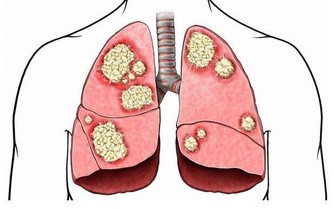

(6) 月經紊亂,可出現月經紊亂、出血。若雙側卵巢均被癌組織破壞,可引起月經失調和閉經,肺轉移可出現咳嗽、咳血、胸水;骨轉移可造成轉移灶局部劇疼。腸道轉移可有便血,嚴重的可造成腸梗阻。